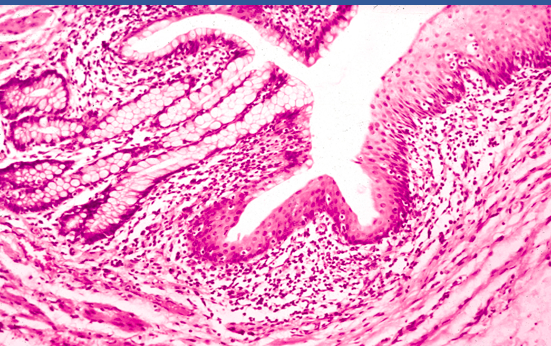

What is this?

Mucosa of the recto—anal junction. The simple columnar epithelium with tubular glands that lines the rectum (left side) changes abruptly to stratified squamous epithelium in the anal canal (right side), as seen in this longitudinal section.

Can distinguish between gastroesophageal junction because there are no gardiac glands,